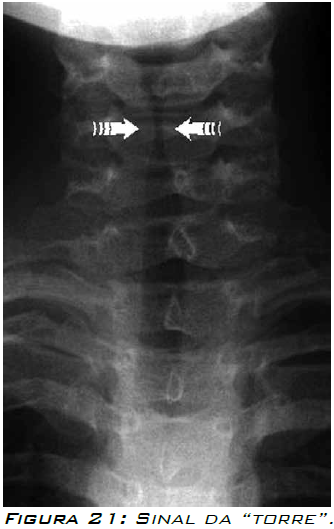

“Sinal da torre” ou “Sinal da ponta do lápis”.

Área correspondente ao estreitamento infraglótico.

Pode estar ausente em pacientes com crupe e pode ser identificado em outros que não têm a doença.